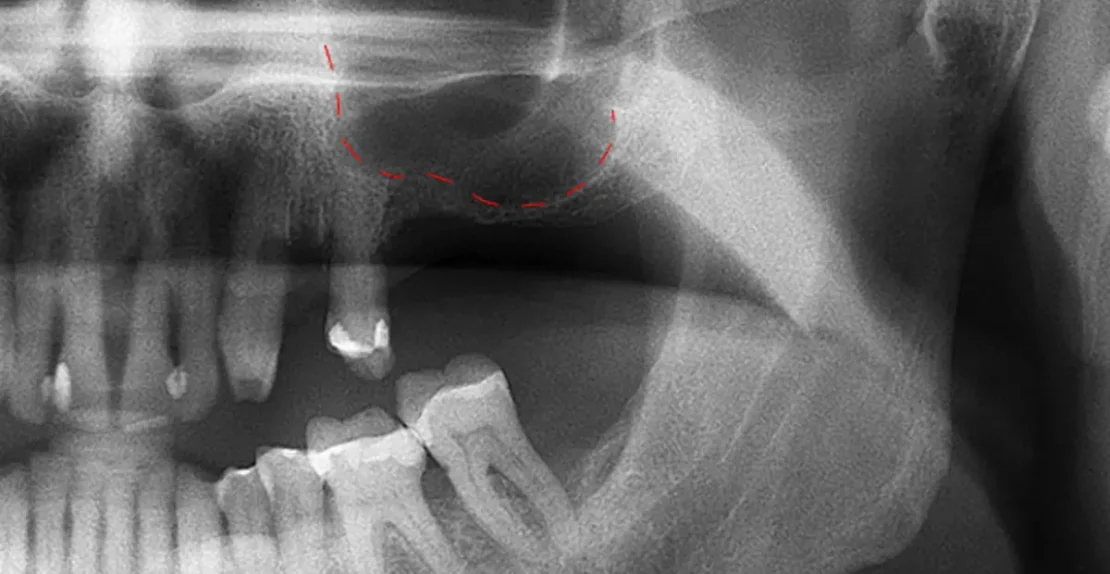

23 مهر مقالات, مقالات ترمیم دندان توضیح اینله و انله به زبان ساده + شرح مراحل 29 آذر 1404 توسط آرتمان درمان 2 دیدگاه در دندانپزشکی چندین نوع روش برای ترمیم دندانهای آسیب دیده و یا دچار پوسیدگی وجود دارد. ما در آرتمان درمان بسته به اینکه مقدار آسیب دید... ادامه مطلب